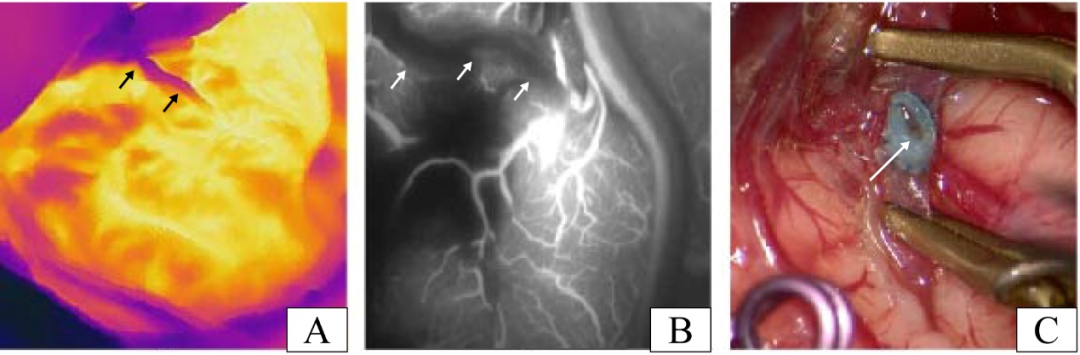

图4. 一位血管吻合口不通畅的患者。(A)该患者释放血管夹后的红外热成像结果(黑色箭头表示STA)。(B)该患者释放血管夹后的ICG-VA图像结果(白色箭头表示STA)。(C)在剪开颞浅动脉后发现血栓,是导致该病例血管吻合口不通畅的原因(白色箭头表示吻合口的血栓)。

其中一名患者术中应用红外热成像评估后怀疑吻合口通畅性不足,而吻合口的ICG-VA评估结果证实确实存在吻合口梗阻(图4A,B)。打开颞浅动脉观察吻合口内部情况后,从图4C可以看到血栓,我们考虑该血栓形成是本例吻合口梗阻的原因。这进一步证明了红外热成像和ICG-VA在评估吻合口通畅性方面的一致结果。随后,该病例通过拆除吻合口并清除血栓后重新进行了吻合。